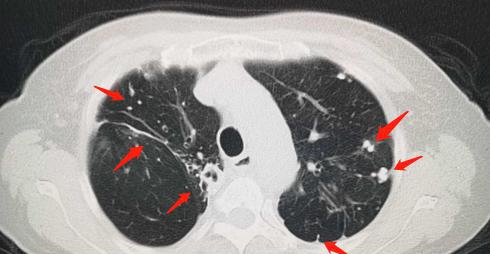

陈旧性肺结核ct图片

陈旧性肺结核ct图片,肺结核的ct图片

肺结核的ct图片

肺结核ct图片

肺结核CT片子图片特点

肺结核ct表现

肺结核ct影像表现特点